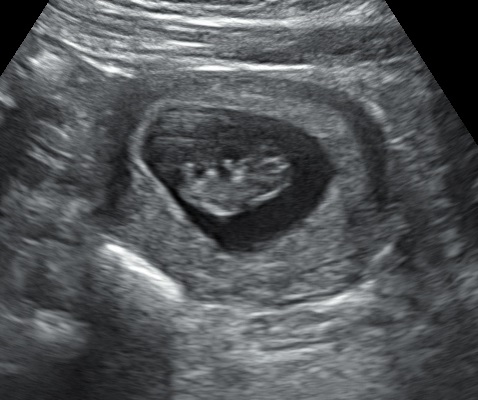

9 weeks + 5 days

This week, baby is back to measuring bang on average for dates (9w5d) & almost 2.9cm long and still has a heart rate in the high 170's. It even wiggled around on the screen for me today!